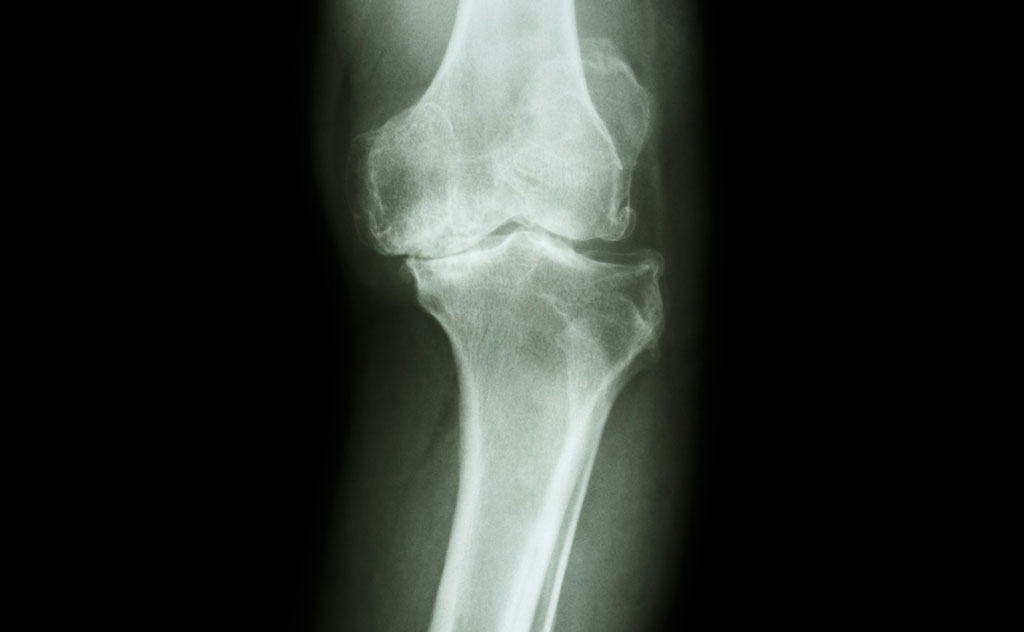

Patients will occasionally have differences in the structure of their hip and knee joints. This is most commonly having “bowed legs” or “knock knees” but can also be conditions such as developmental or congenital dysplasia of the hip.

There are a multitude of different conditions that can lead to abnormalities in the structure of the hip or knee joint.